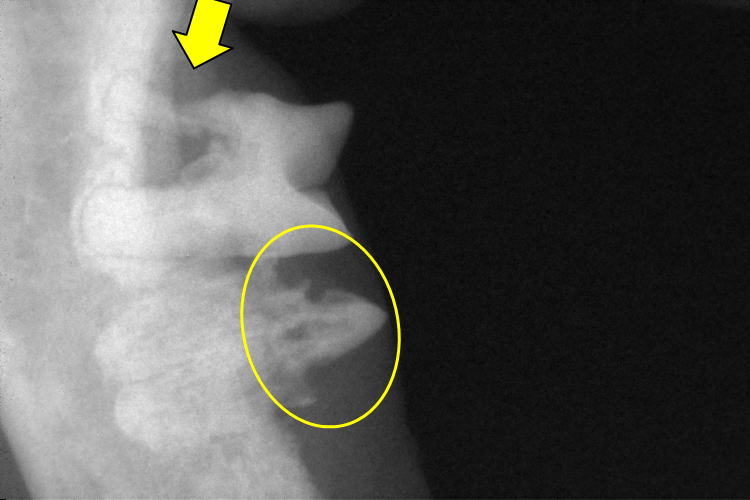

右下顎第2前臼歯(写真上側の歯)と第1後臼歯(写真下側の歯)です。

第2前臼歯は近心根が細くなり(黄色矢印)、吸収している事が確認出来ます。

第1後臼歯は歯冠が吸収し(黄色〇)、歯根はアンキローシスを起こしていました。

これらの検査により、治療を決定します。

今回、右上顎第3前臼歯・左右下顎第1後臼歯の抜歯と

左右下顎第2前臼歯の歯冠切除を実施を決定しました。